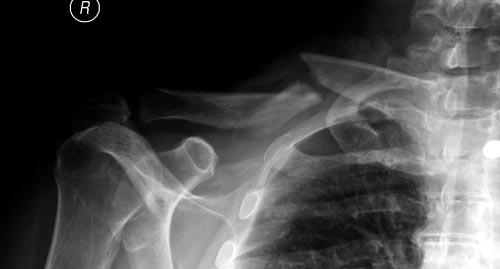

Болезненные ложные суставы надо оперировать, и здесь представлен случай

свежего болезненного ложного сустава, оперированного через 4 месяца.

Освобожден средний фрагмент и боковая компрессия лагированием, фиксация

пластиной..

Вложение не в текстовом формате было извлечено…

Имя     : Clavicle 2.jpg

Тип     : image/jpeg

Размер  : 26600 байтов

Описание: отсутствует

Url     : http://weborto.net:8080/pipermail/ortho/attachments/20141124/0ee515fb/attachment-0034.jpg